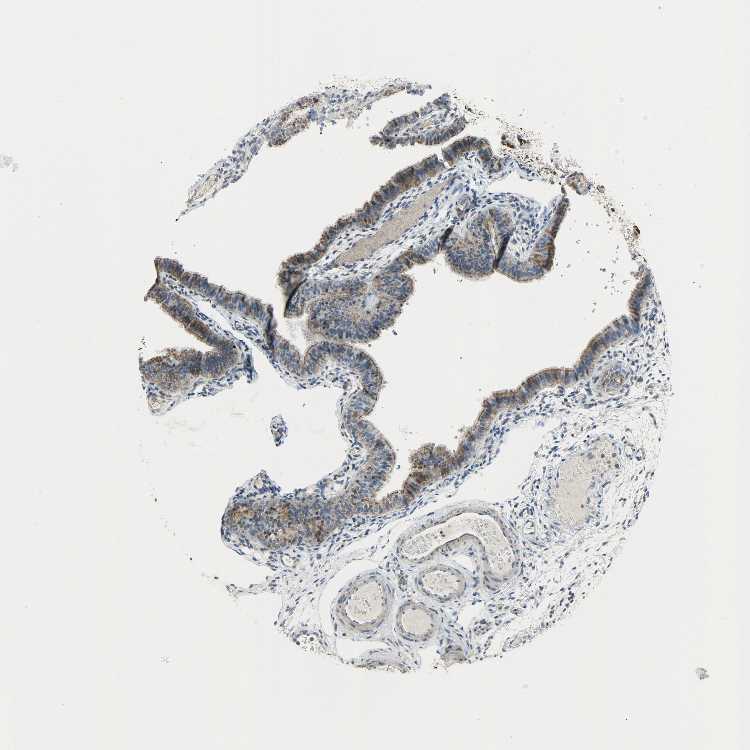

TISSUE PRIMARY DATA FALLOPIAN TUBE Show tissue menu

FALLOPIAN TUBE - Antibody stainingi

Antibody staining in the annotated cell types in the current human tissue is reported as not detected, low, medium, or high, based on conventional immunohistochemistry profiling in selected tissues. This score is based on the combination of the staining intensity and fraction of stained cells.

Each image is clickable and will lead to virtual microscopy that enables deeper exploration of all samples and also displays staining intensity scores, fraction scores and subcellular localization as well as patient and tissue information for each sample.

Antibody HPA019007Antibody CAB004641

Glandular cells MediumMedium